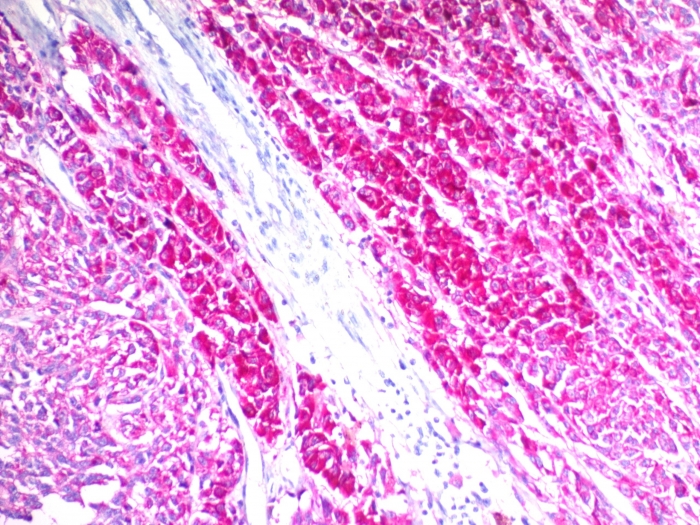

Formalin-fixed, paraffin-embedded human melanoma stained with CD63 Mouse Monoclonal Antibody (SPM524) (AEC chromogen).

This MAb recognizes protein of 26kDa-60kDa, which is identified as CD63. Its epitope is different from that of MAb LAMP3/529. The tetraspanins are integral membrane proteins expressed on cell surface and granular membranes of hematopoietic cells and are components of multi-molecular complexes with specific integrins. The tetraspanin CD63 is a lysosomal membrane glycoprotein that translocates to the plasma membrane after platelet activation. CD63 is expressed on activated platelets, monocytes and macrophages, and is weakly expressed on granulocytes, T cell and B cells. It is located on the basophilic granule membranes and on the plasma membranes of lymphocytes and granulocytes. CD63 is a member of the TM4 superfamily of leukocyte glycoproteins that includes CD9, CD37 and CD53, which contain four transmembrane regions. CD63 may play a role in phagocytic and intracellular lysosome-phagosome fusion events. CD63 deficiency is associated with Hermansky-Pudlak syndrome and is strongly expressed during the early stages of melanoma progression.